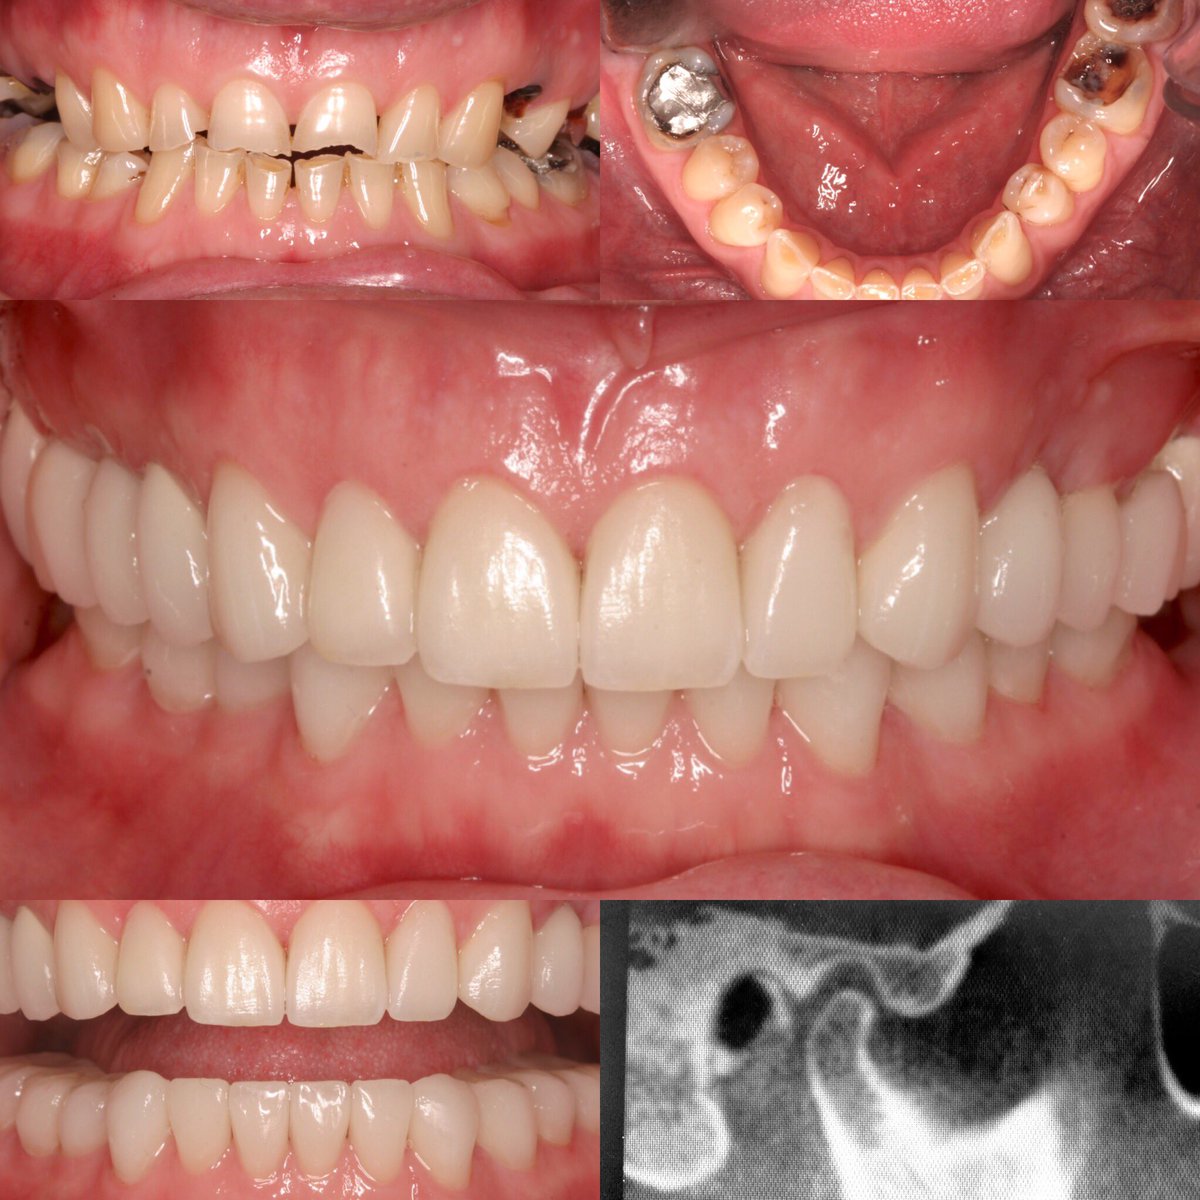

Presentation is key.

Dr Apa presents himself and work in top notch fashion.

Ask us how we can help… instagram.com/p/48blGnR8qT/